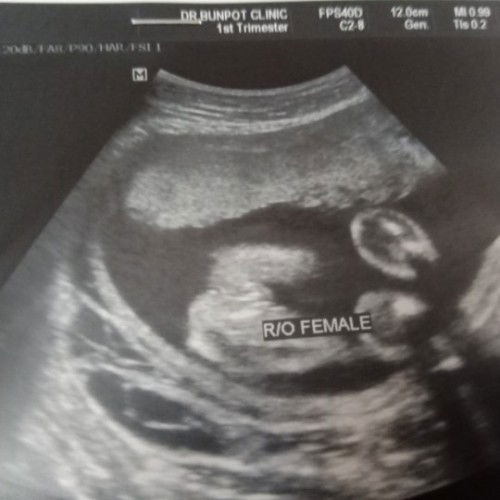

ภาพอัลตร้าซาวช่วยดูหน่อยจ้าว่าใข่เพศหญิงชัวๆเลยไหม 😀😀

ตอนนี้16วีค4 สามารถรู้เพศได้กรือยังคะ

ตอนนี้16วีค4 อยากทราบว่าสามารถเห็นเพศได้หรือยังคะ